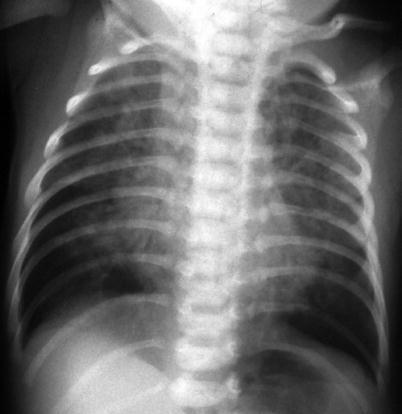

Chlamydia Pneumonia

Chlamydia trachomatis is an obligate intracellular parasite. Genital chlamydial infection is recognized as the world’s most common sexually transmitted disease, and the high prevalence in women of childbearing age results in exposure of neonates during childbirth. Chlamydia pneumonia is a neonatal infection acquired after passage of the fetus through the cervix and vagina. The infant typically presents at 3–6 weeks of age with respiratory symptoms and occasional pulmonary hemorrhage. C. trachomatis should be suspected in infants who are afebrile or nontoxic and have a dry cough. These patients often have a peripheral eosinophilic pleocytosis, sometimes with concomitant conjunctivitis (Ostapchuk et al. 2004). Most chest radiographs show bilateral hyperaeration and diffuse infiltrates with a variety of radiographic patterns including interstitial, reticular nodular, atelectasis, coalescence, and bronchopneumonia (Radkowski et al. 1981) (Fig. 13.16).

Fig. 13.16.

Chlamydia pneumonia. Radiograph of an afebrile 2-week-old girl with dry cough shows bilateral hyperaeration and diffuse interstitial infiltrates, appearing coalescent on the right